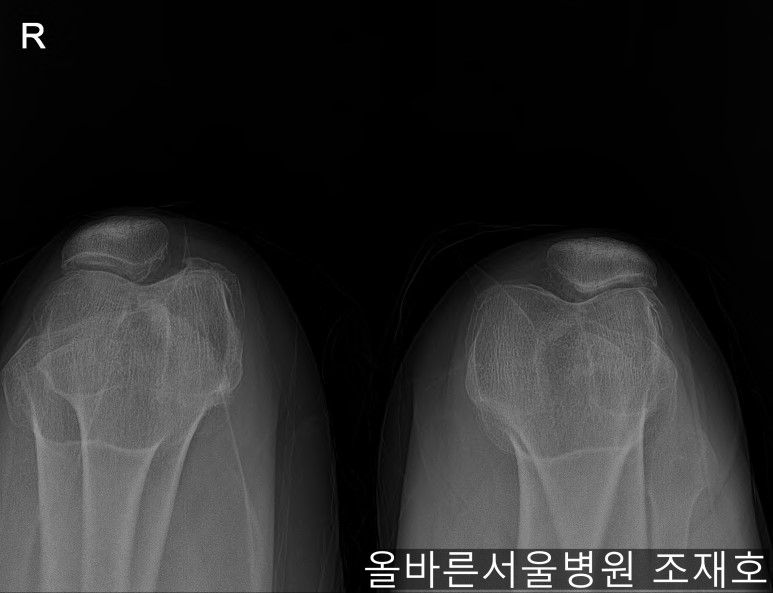

仅通过放射线片子观察到:右膝由于炎症严重,内侧胫骨及股骨已接触在一起,向内测严重变形。

左膝虽然也观察到了炎症,但远不如右膝严重。

如果通过X光片也观察到相同的病症,可以判断内侧关节的软骨大部分都损伤了。

观察膝盖下肢排列的扫描图像可看到右腿严重变形,身体中心向内倾斜。